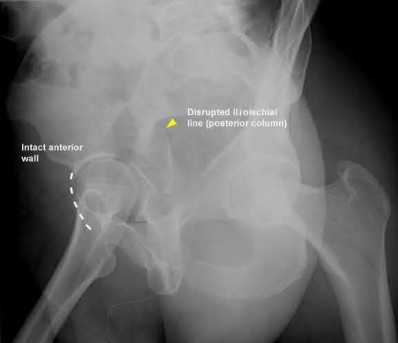

Which of the following will most likely result with the use of a fracture table when treating the injury shown in Figures A and B?

1) Internal malrotation deformity

2) External malrotation deformity

3) Recurvatum deformity

4) Varus deformity

5) Valgus deformity

The fracture table has been shown to induce an internal malrotation deformity when it is used for treating femoral shaft fractures.

Intramedullary nailing with reaming of the bone and static locking of the nail is the treatment of choice for femoral shaft fractures in adults. The fracture table has been used with excellent results. Compared to manual traction, the fracture table provides an advantage as only one assistant is necessary.

However, it may limit access to the patient if other body areas are injured. Additionally, the fracture table has been shown to induce an internal malrotation deformity, which results from internally rotating the limb to facilitate access to the starting point and to improve visualization of the hip in the lateral plane. Rotation may also be difficult to assess clinically once the limb is positioned and draped.

Kelly et al. performed a retrospective study to determine complications associated with the use of the fracture table in pediatric femoral fractures.

They found 8 palsies related to positioning. They also found that patients who developed nerve palsies were significantly heavier. They ultimately concluded that the fracture table is safe for fixation but every effort should be made to minimize time in traction to avoid iatrogenic nerve palsy, particularly in heavier children (> 80 kg).

Stephen et al. performed a randomized study comparing the fracture table and manual traction when nailing femoral shaft fractures. They found that internal malrotation was significantly more common when the fracture table was used. Operative time was also greater for the fracture table group. There were no other differences in complications. They concluded that manual traction is an effective technique that decreases operative time and improves the quality of reduction.

Figures A and B are AP radiographs demonstrating a femoral shaft fracture. Incorrect Answers:

Answers 2, 3, 4, & 5: Internal malrotation has been shown to be a risk when

using a fracture table to treat femoral shaft fractures by intramedullary nailing.